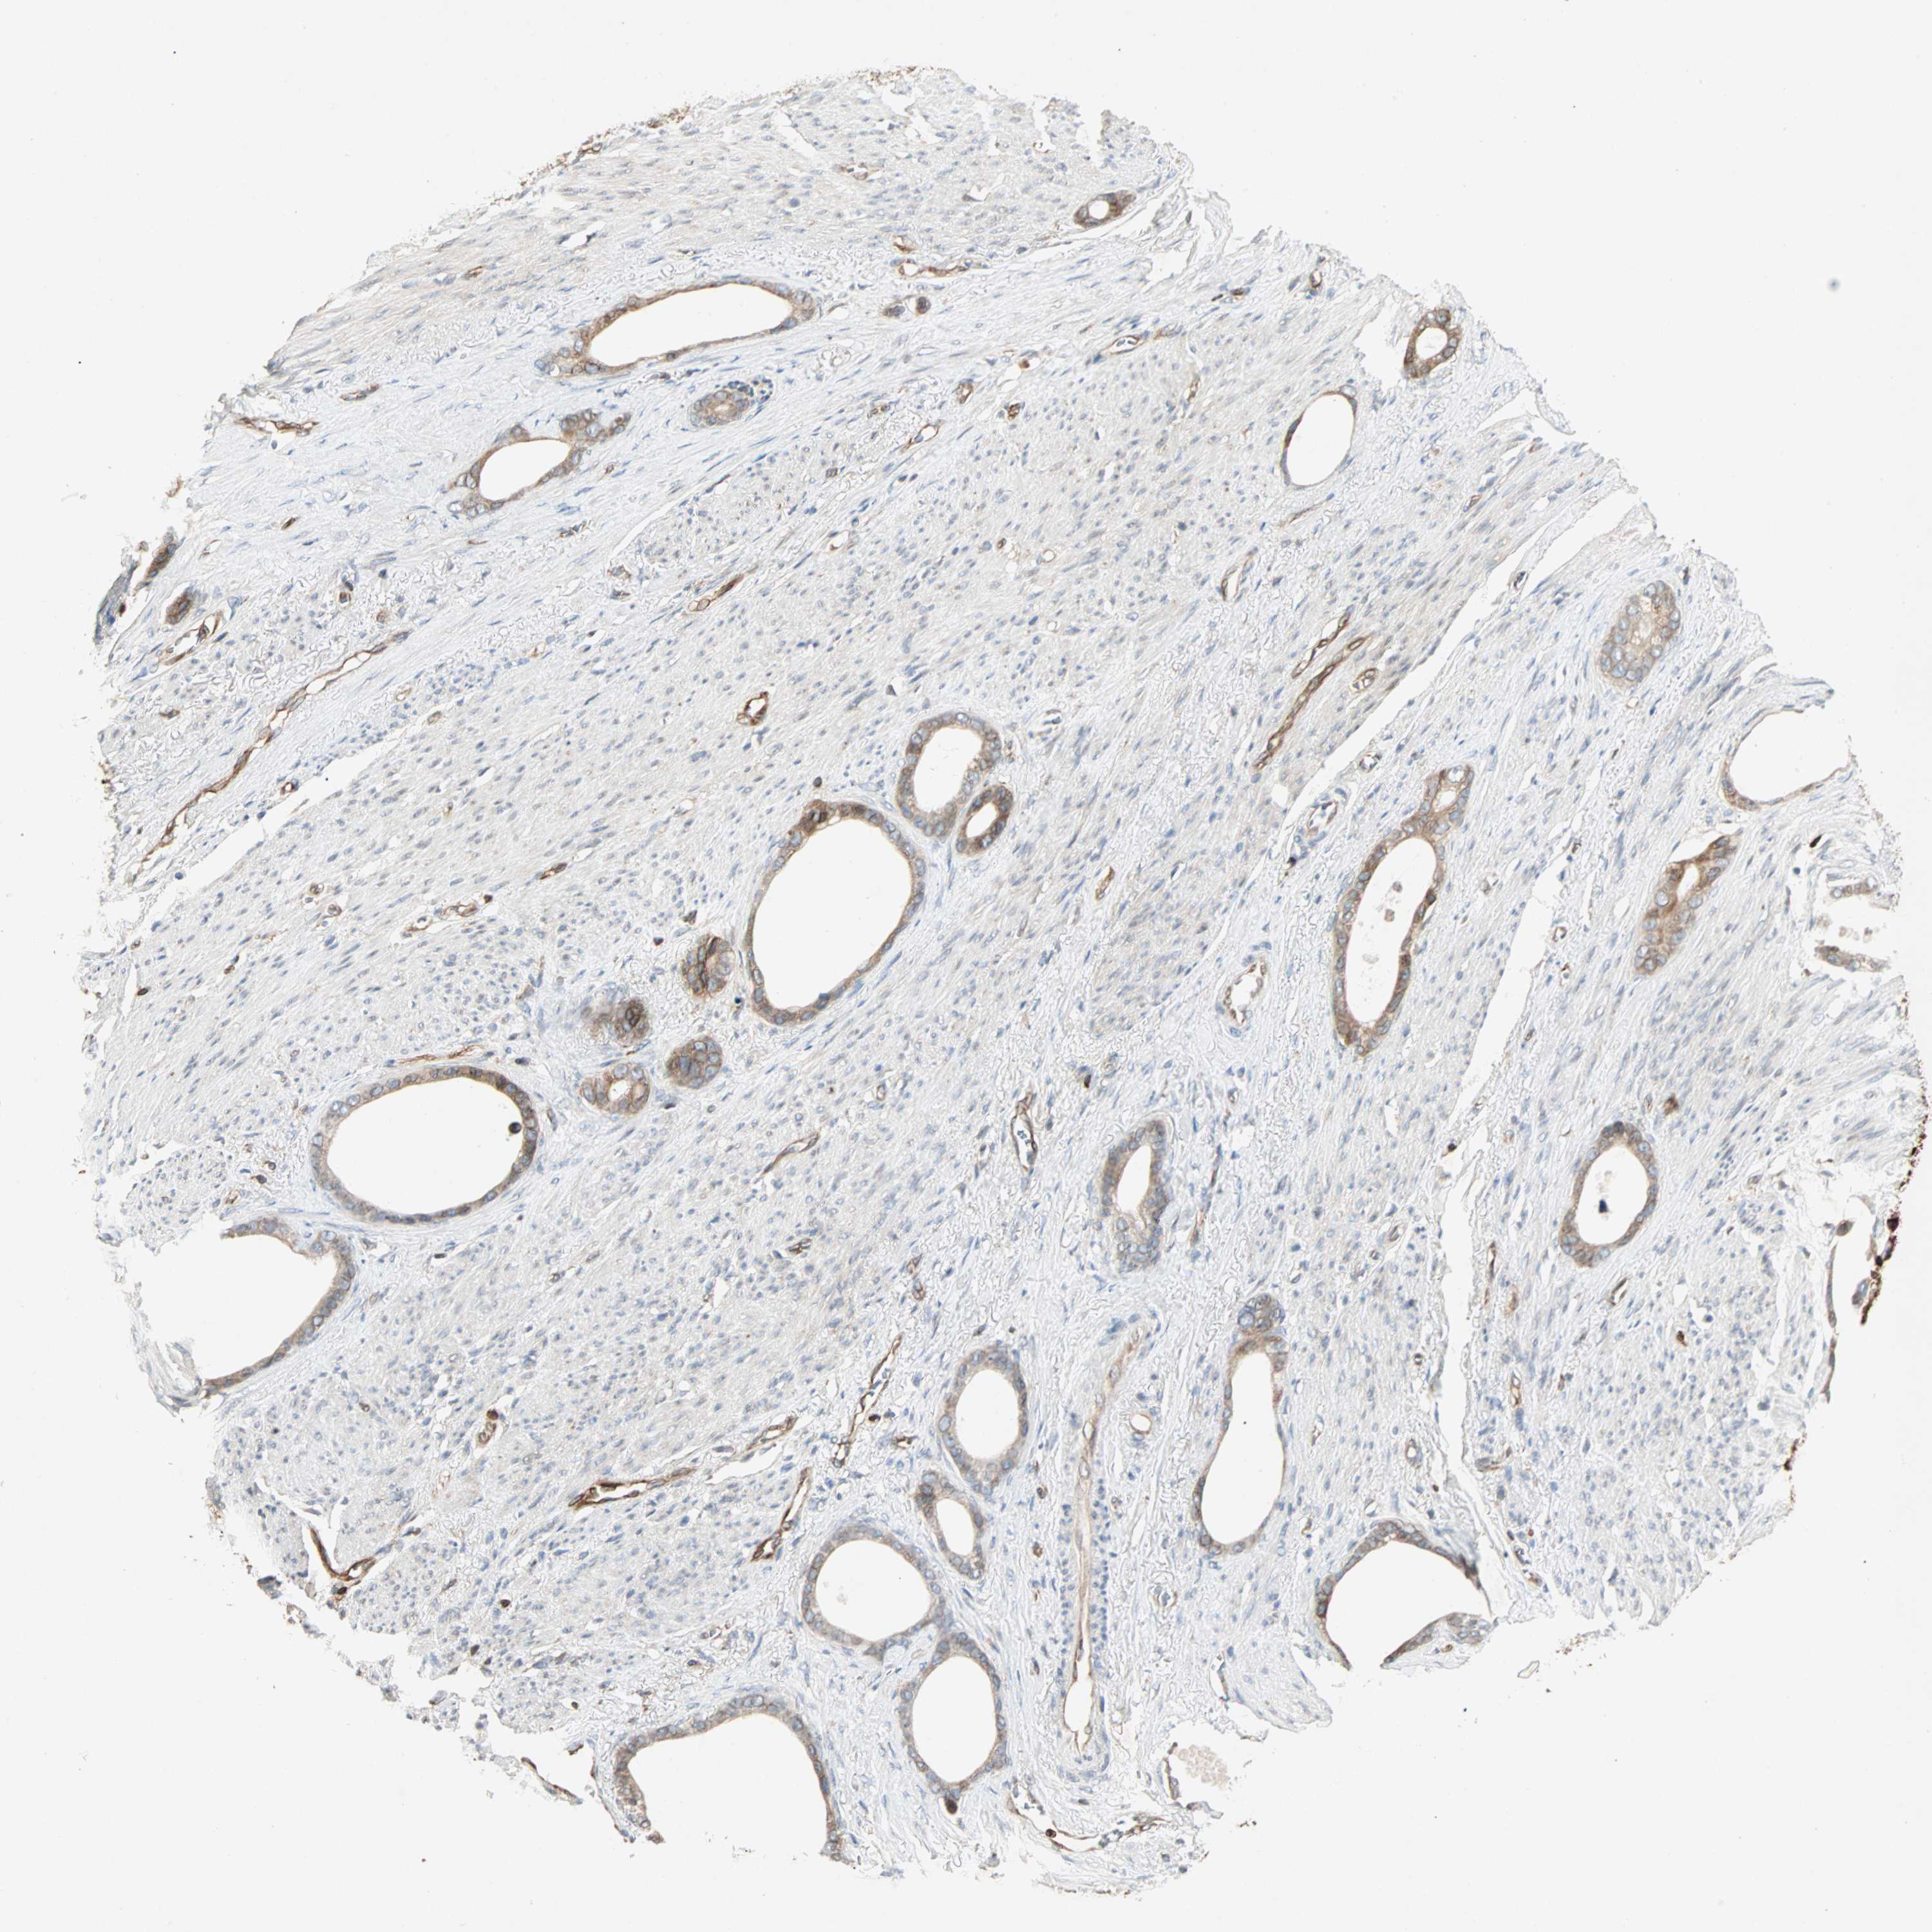

STOMACH CANCER - Protein expressioni

A mouse-over function shows sample information and annotation data. Click on an image to view it in a full screen mode. Samples can be filtered based on level of antibody staining by selecting one or several of the following categories: high, medium, low and not detected. The assay and annotation is described here.

Note that samples used for immunohistochemistry by the Human Protein Atlas do not correspond to samples in the TCGA dataset.

Antibody stainingi

Antibody staining in the annotated cell types in the current human tissue is reported as not detected, low, medium, or high, based on conventional immunohistochemistry profiling in selected tissues. This score is based on the combination of the staining intensity and fraction of stained cells.

Each image is clickable and will lead to virtual microscopy that enables deeper exploration of all samples and also displays staining intensity scores, fraction scores and subcellular localization as well as patient and tissue information for each sample.

Antibody HPA007066

Staining

High

Medium

Low

Not detected

Intensity

Strong

Moderate

Weak

Negative

Quantity

>75%

75%-25%

<25%

None

Location

Nuclear

Cytoplasmic/membranous

Cytoplasmic/membranous,nuclear

Adenocarcinoma, NOS